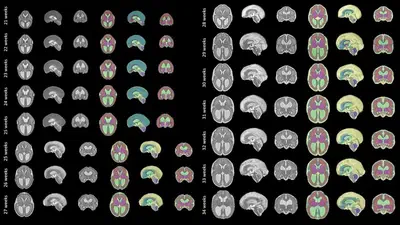

Our publication in Open Research Europe details the methodology and software tools behind our open access atlas of the developing brain in fetuses with spina bifida aperta (SBA) between 21 weeks and 34 weeks of gestation. This first-time atlas will allow researchers to perform measurements of the brain’s anatomy and to study its development in a large population of unborn babies with SBA.

A total of 90 high resolution 3D Magnetic Resonance Images (MRI) scans taken of fetuses with SBA in the womb were collected, analysed and processed to develop the atlas. Developed by Dr Lucas Fidon, the atlas can allow researchers to perform more accurate measurements in fetuses with SBA.

The researchers selected the 21–34 week period of the development of the fetal brain in SBA as surgery performed while the baby is still in the womb is currently completed prior to 26 weeks of gestation.